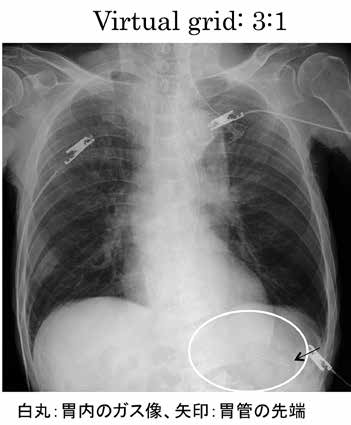

また、今回導入されたDRシステムは、撮影後の画像にCRシステムと同様に階調処理や空間周波数処理などの画像処理が行えることである。それに加え、散乱X線除去として一般的にグリッドを用いて撮影しているが、本装置では、グリッドを使わずにコントラストを改善し、ノイズを抑制する技術(Virtual Grid;VG)が搭載されている。

この技術では、検査を実施した時の撮影条件(管電圧、mAs値、撮影距離)の情報と画像の画素値から、被写体厚を推定しそれを元に、散乱X線含有率を画素単位で算出する。また、仮想グリッドのグリッド比率により決定される散乱X線除去率を用いて散乱X線相当分の画素値を減算することで、グリッド透過後の画像を生成し画像コントラストを改善している2)。仮想グリッド比も1:1〜20:1まで選択でき、撮影別のメニューに組み込むことも可能であり、撮影後に仮想グリッドを入れたり、グリッド比を変更したりできる。このことは、グリッドを使用しないことで、患者の被ばく線量の低減はもちろんだが、実グリッド使用によるX線束の斜入による画像のムラを回避できるなどの利点がある。撮影部位ごとに適切な使用はもちろんだが、散乱X線の多い腹部や胸部の縦郭内のカテーテル先端の確認や胃管挿入後の撮影などに使用している(図4)。

a Gridなしの撮影なので、階調を調整し、画像全体を黒くし、胃管の位置が見えるように出力した(先端は不明瞭)。

b 胃管の位置を調整し、撮影依頼がきた。gridなしで撮影し、virtual grid を3:1に設定し、肺野の見える通常の画像処理でも胃管の位置が確認できた。